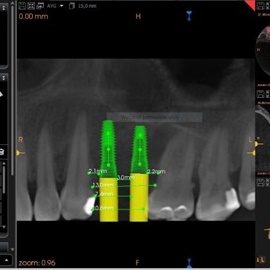

Lat 50, pół roku przed rozpoczęciem leczenia implantologicznego przestał palić papierosy. Znacząca poprawa higieny, pacjent silnie zmotywowany. Po regeneracji kości i rekonstrukcji tkanek miękkich odbudowa sześciu zębów na koronach porcelanowych. Na zdjęciu widoczna ilość i jakość tkanki kostnej po rekonstrukcji. W porównaniu ze stanem początkowym uzyskano znaczącą poprawę warunków kostnych nie do osiągnięcia metodami sterowanej regeneracji kości z użyciem reklamowanych markowych błon kolagenowych i dosypaniem kości z butelki.